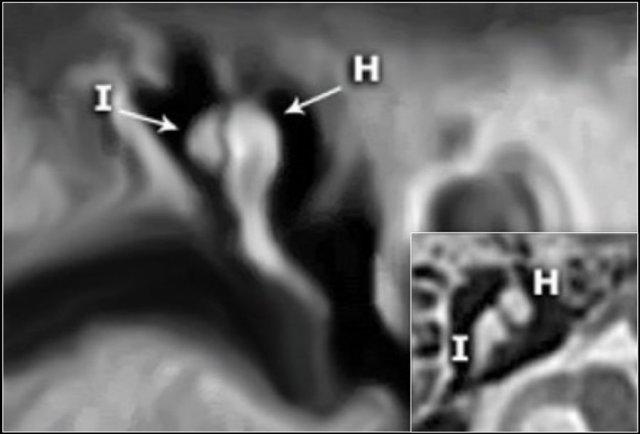

Chuỗi xương con

Trong nhiều hình minh họa, xương đe thường được vẽ kết nối về phía trong với xương búa, tuy nhiên điều này không chính xác.

Trên ảnh tái tạo mặt phẳng coronal bên trái, có thể thấy rõ ràng rằng xương đe nằm ở phía sau ngoài so với đầu xương búa.

Ngành dài của xương đe sau đó chạy xuống dưới và vào trong để tiếp khớp với xương bàn đạp.